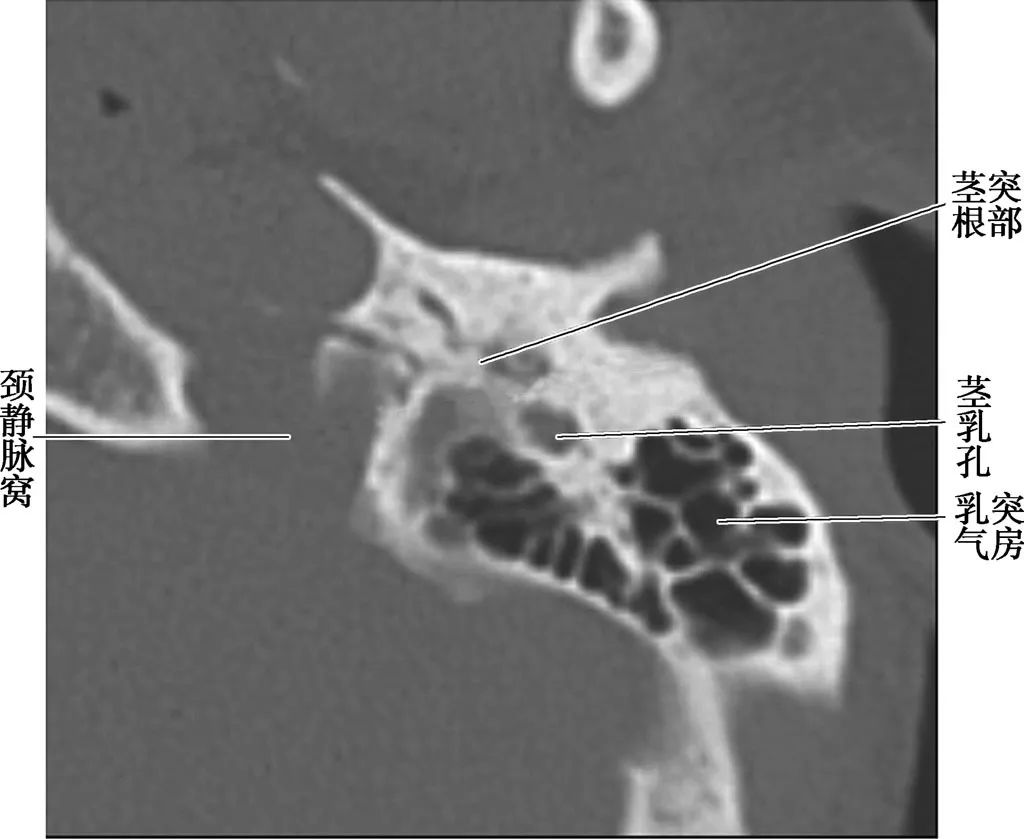

耳部及其周围的重要解剖结构 (CT横断面)

A.上骨半规管层面;B.外骨半规管层面;C.前庭窗层面;D.耳蜗层面;E.颈动脉管层面1.上骨半规管;2.弓形下窝;3.总骨脚;4.后骨半规管;5.外骨半规管;6.内耳道;7.耳蜗;8.面神经管迷路段;9.膝状神经节;10.前庭;11.上鼓室;12.乳突窦入口;13.乳突窦;14.鼓膜张肌;15.锤骨头;16.砧骨体;17.前庭窗;18.前庭导水管;19.圆窗;20.鼓岬;21.锤骨颈;22.砧骨长脚;23.面神经隐窝;24.锥隆起;25.鼓室窦;26.颈动脉管;27.咽鼓管;28.耳蜗导水管;29.颈静脉球